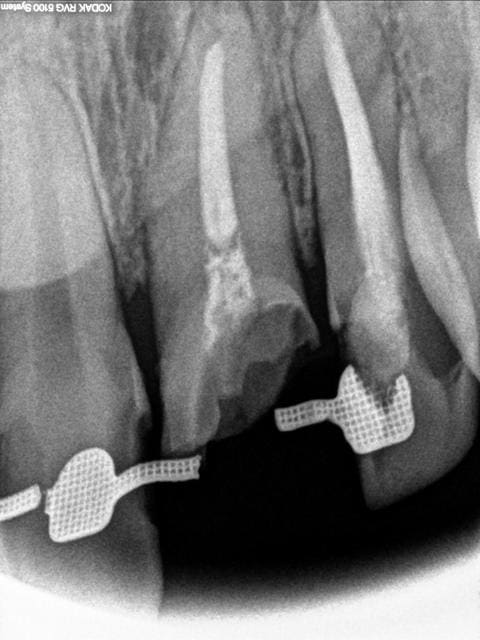

les radios

Pano ziyd19 - Eugenol

R21 q4vskw - Eugenol

Il y a un rapport couronne/racine 1/1

Les limites actuelles sont juxtaosseuses. Le canal est hyper large.

Je crains la fracture de la racine, un collet inesthetique, une migration vestibulaire...

Je suis plus traction ortho qu'elongation, mais trauma ancien, la refaire bouger ne va pas declencher une rhyzalise...